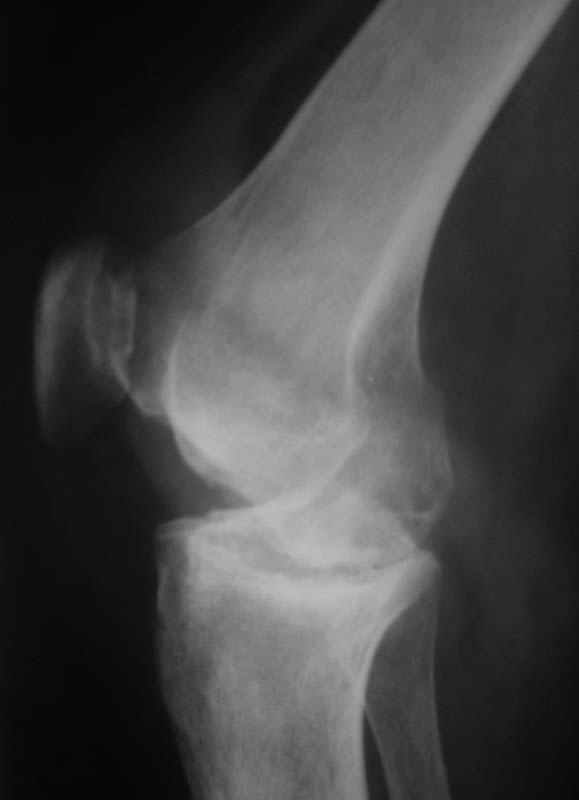

Уважаемые коллеги! Женщина, 28 лет. Страдает ревматоидным полиартритом, гормонозависима. 6 месяцев назад перенесла тотальное эндопротезирование левого тазобедренного сустава по поводу протрузионного коксита.

Использована цементная версия с пластикой дна впадины измельченной аутокостью и гранулами гидроксиапатита. Субъективное улучшение после операции. Улучшилось и стабилизировалось общее состояние. В настоящее время затруднено передвижение из-за поражения правого коленного сустава. Болезненный и <болтающийся> сустав. Предполагается замена сустава протезом без сохранения задней крестообразной связки. Возможные варианты? Заранее благодарю! С уважением, А.В.Владзимирский Донецкий НИИ травматологии и ортопедии Донецк, Украина